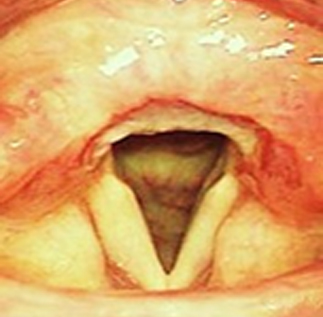

후비루 증상은 부비동 엑스레이나 비강 내시경을 통하여 비부비동염 여부를 확인해야 하며, 기침형 천식은 기관지 유발 시험, 호기 산화질소, 객담 호산구 검사 등으로 진단할 수 있습니다. 한편 위식도 역류 질환은 식도로 역류된 위속의 내용물로 인해 불편한 증상이나 합병증이 유발되는 상태를 말하며, 24시간 식도 산도 검사나 위내시경을 통하여 진단할 수 있습니다. 위산이 식도를 넘어 인두와 후두까지 역류하여 점막을 자극하는 경우 후두 내시경을 통하여 인후두 역류 질환을 진단할 수 있습니다.

상기도 기침 증후군 기침형 천식 위산 역류 질환

치료 전 기관지 유발 시험 검사 위식도 역류 질환

img img img

치료 후 기관지 유발 시험 검사 양성 인후두 역류 질환